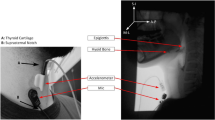

Sazonov, E. S., S. A. Schuckers, P. Lopez-Meyer, O. Makeyev, E. L. Melanson, M. R. Neuman, and J. O. Hill. Toward objective monitoring of ingestive behavior in free-living population. Obes. Res., 2009. doi:10.1038/oby.2009.153.

Sazonov, E. S., S. A. Schuckers, P. Lopez-Meyer, O. Makeyev, N. Sazonova, E. L. Melanson, and M. R. Neuman. Non-invasive monitoring of chewing and swallowing for objective quantification of ingestive behavior. Physiol. Meas. 29(5):525–541, 2008.